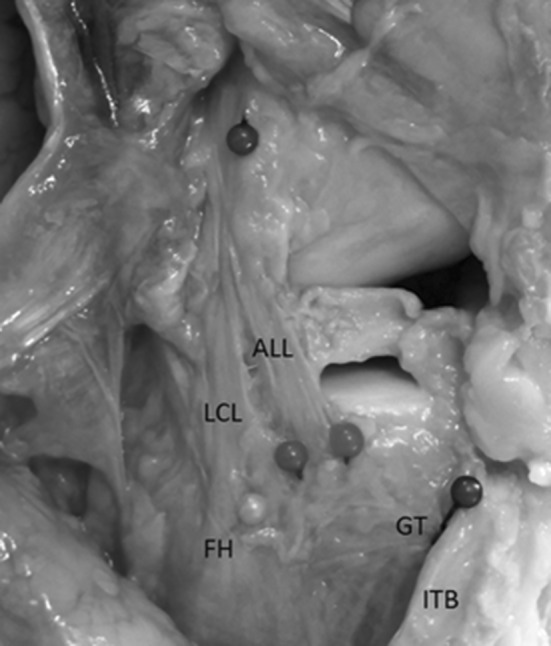

Eleven fresh-frozen cadaveric knees [nine female; two male; median age 79 years (range 71–88 years)] underwent a standardised anatomical dissection. The ALL was identified by using a dissection technique that closely mimicked that of Caterine et al. [1]. This is also similar to that used in previous studies [10, 13]. The lateral skin was removed as a large flap and the iliotibial band (ITB) was exposed from its insertion [Gerdy’s tubercle (GT)] to the mid-thigh. The ITB was transected 200 mm proximal to its insertion and care was taken to elevate this without damaging the deep structures. Loose connective tissue was removed to demarcate the anterolateral structures. The tibia was internally rotated, throughout the dissection, to identify structures under tension. The lateral collateral ligament (LCL) was defined (as an easily identifiable structure) and dissection proceeded anteriorly to isolate the tight structure (the ALL) and remove tissue not under tension in this internally rotated position. Once isolated, the attachments of the LCL and ALL were defined, along with the centre of the fibula head (FH) and GT (Fig. 1). Other groups have chosen to either remove the ITB from distal to proximal [3, 22] or the entire extensor apparatus [21]. We felt that both these techniques conferred increased risk of inadvertent damage to the ALL structure (due to the close proximity of structures around GT) so chose to elevate the transected ITB from proximal to distal.

Fig. 1.

Photograph of dissected specimen. ALL anterolateral ligament, LCL lateral collateral ligament, FH fibula head, GT Gerdy’s tubercle, ITB iliotibial band